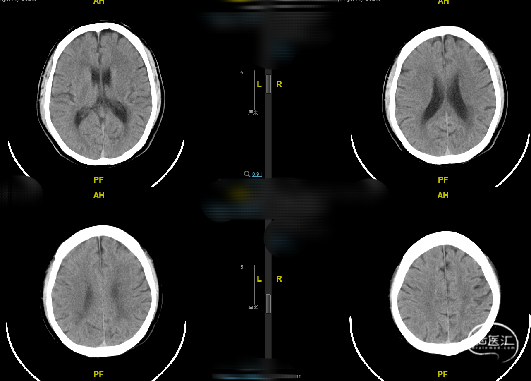

随访:患者术后一般情况好,神经系统查体无明显异常,复查头颅CT未见新发梗死/出血,血压控制良好,好转出。

随访:患者术后一般情况好,神经系统查体无明显异常,血压控制良好,术后第二天复查头颅CT未见出血/梗死并发症。